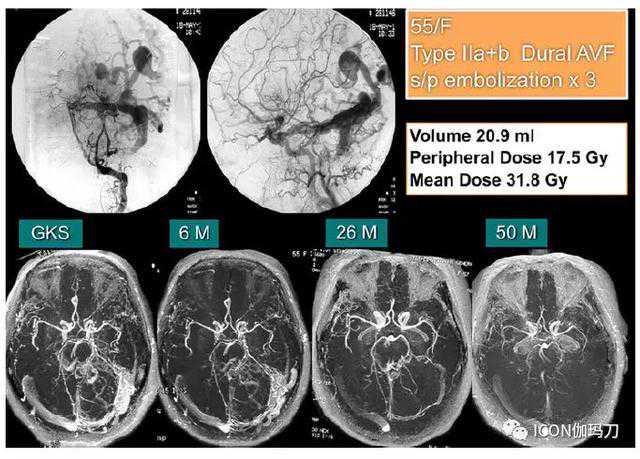

图4。非海绵窦硬脑膜动静脉瘘(DAVF)的病例图解。一例55岁的女性患者有右侧横窦-乙状窦硬脑膜动静脉瘘伴搏动性耳鸣。她接受过三次经动脉栓塞治疗(TAEs),但症状依然存在。伽玛刀放射外科治疗前的CognardIIa+IIb型硬脑膜动静脉瘘伴皮层静脉引流。边缘剂量为17.5Gy,经单次伽玛刀放射外科治疗照射硬脑膜动静脉瘘病灶,照射体积为20.9立方厘米。在伽玛刀放射外科治疗后26个月,硬脑膜动静脉瘘分流部分被关闭,恼人的症状也随之得到解决。伽玛刀放射外科治疗后50个月MRA显示完全消失。